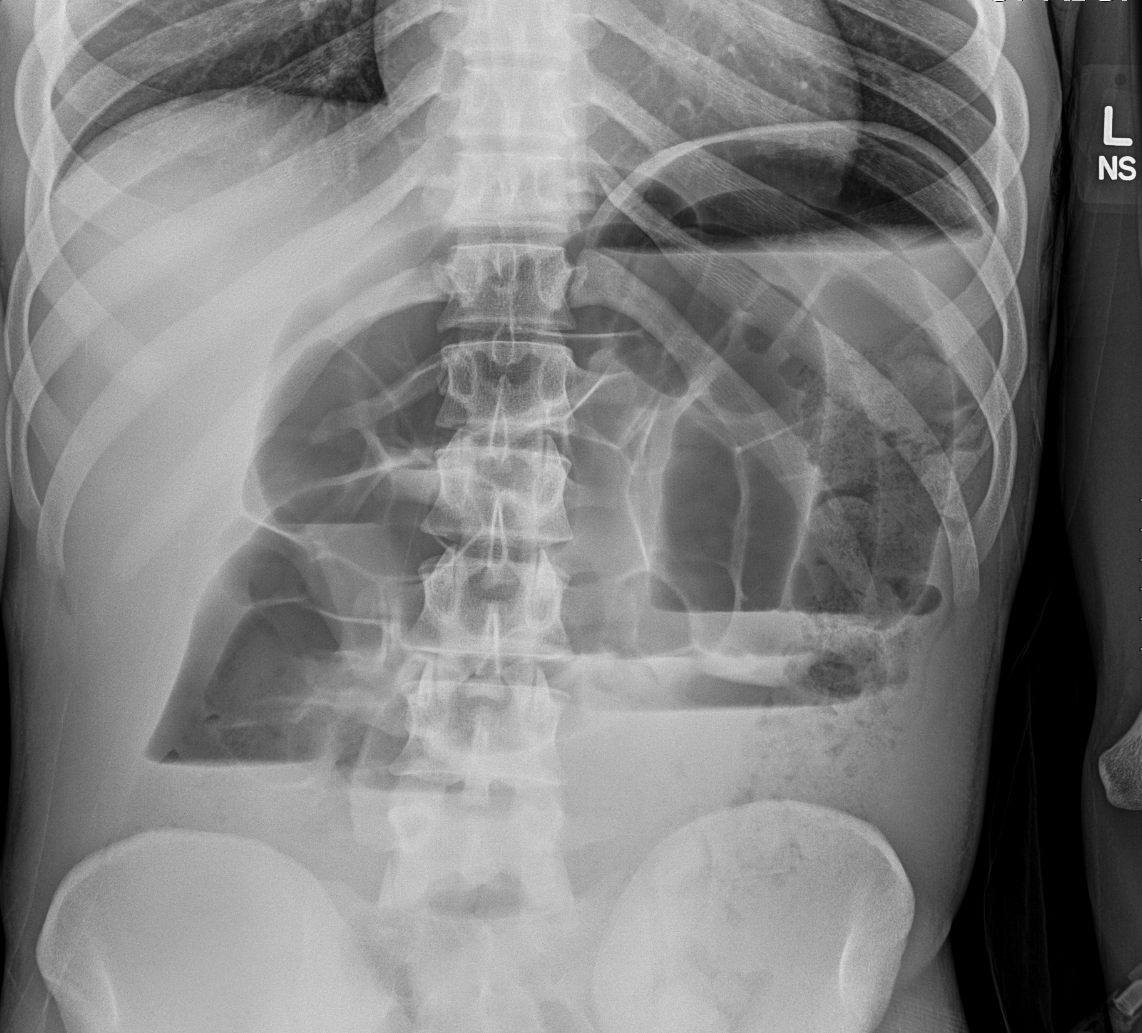

Info Images Findings Impression Reco/Acuity Case Images View Images / Launch Visage Case Notes History 2-month-old presents with decreased right arm movement, increased fussiness, and increased sleepiness for 2 days. Suspected non-accidental trauma. Exam Skeletal survey Prior Study none Dicom View Reference Material

Section 1 Submit Findings CB1550 Findings Skeletal Survey - Technique Check Skull AP/Lat Yes No Cervical and Thoracolumbar spine Yes No Chest X-Ray Yes No Ribs – Left/Right Oblique Yes No Abdominal X-Ray Yes No Pelvis with both hips Yes No Bilateral Humerus, Forearm, Hand Yes No Bilateral Femur, Tibia/fibula, feet Yes No Any additional lateral views of the extremities Yes No The exam is over or under penetrated. Yes No The exam may or may not be limited by overlying structures or soft tissues, body habitus, patient positioning, support devices, or motion. Yes No The area of concern is indicated by the patient, technologist, or care provider. Yes No The area of concern is included on the exam. Yes No Soft Tissues There is soft tissue swelling, indistinctness of fat/muscle planes, gas, or laceration in the area of clinical concern. Yes No There is an effusion, fat pad displacement, or fat fluid level. Yes No There is a radiodense or lucent foreign body. Yes No There are other densities, calcifications, post-surgical changes, or support devices in the soft tissues. Yes No Any support lines/tubes. Yes No Bone There is a break or interruption of the continuity of the cortical or cancellous bone. Yes No There is overriding of the trabeculae with apparent sclerosis. Yes No There is displacement of a fracture fragment. Yes No There is bowing of the bone in addition to the fracture at the apex of the bowed bone concerning for the greenstick. Yes No There is a spiral fracture of the leg concerning for toddler’s fracture. Yes No There is abnormal angulation or bulging of the cortical surface relative to the normal cortex which could be from a buckle or torus fracture. Yes No There is a displaced fragment which may be from avulsion by a tendon, ligament, or joint capsule or from a comminuted or other fracture. Yes No The stress trabeculae or other trabeculae of the cancellous bone are interrupted or otherwise abnormal. Yes No There is subperiosteal or endosteal reaction which could indicate a healing or subacute fracture or other abnormality. Yes No There is hard/soft callus formation. Yes No There is remodeling of the bone. Yes No There is a corner fracture or metaphyseal lesion that could be from nonaccidental trauma. Yes No There are multiple fractures of different ages. Yes No There are vertebral body/spinous process fractures. Yes No There are rib fractures. Location - posterior or lateral. Yes No There is scapular/sternal fracture. Yes No There are fractures of the digits. Yes No There are wormian bones. Yes No There are intrasutural bones. Yes No There is metaphyseal abnormality (lucencies, increased density, erosion) which may be from something other than injury such as stress, metabolic disease (e.g. rickets with loss or distortion of the zone of the provisional calcification), neoplasm (e.g. leukemia), heavy metals, inflammation, or infection. Yes No There are metaphyseal spurs. Yes No There are bony deformities involving multiple bones. Yes No The bones are gracile. Yes No There are non-healing fractures. Yes No There is/are focal or multifocal lytic/lucent, blastic/sclerotic or mixed density lesion(s) or other abnormality. Yes No Overall bone density is increased or decreased with or without thinning or thickening of the cortical or cancellous bone. Yes No Growth plates, ossification centers, apophyses The growth plate(s) is/are abnormal. Yes No There is widening of the physis from a fracture with or without displacement of the epiphysis (Salter-Harris I). Yes No There is a fracture through the physis which then extends into the metaphysis with or without angulation or displacement (S-H II). Yes No There is a fracture through the physis which then extends into the epiphysis and is intra-articular, with or without angulation or displacement (S-H III). Yes No There is a fracture through the metaphysis, physis, and epiphysis which extends into the joint space with or without angulation or displacement (S-H IV). Yes No There is narrowing of the physis from a compression fracture (S-H V). Yes No The apophysis, epicondyle, secondary ossification center, or accessory ossicle is displaced or otherwise abnormal. Yes No The ossification centers are underdeveloped. Yes No Joints and alignment There is an effusion, fat pad displacement, or fat fluid level. Yes No The epiphysis or subchondral bone is fractured, interrupted, flattened, compressed, impacted, displaced, or otherwise abnormal. Yes No There is an intra-articular loose body or chondrocalcinosis. Yes No The joint is widened, narrowed, dislocated, malaligned, or incongruent. Yes No There is pseudoarthrosis. Yes No Other findings There are developmental changes or other anatomic variants or other existing conditions that may or may not be contributing to symptoms which can or should be further evaluated non-emergently or are otherwise incidental. Yes No The remainder of the exam is abnormal for age. Yes No The lungs show focal airspace opacity. Yes No There is pneumothorax. Yes No There is organomegaly. Yes No There is intra-abdominal calcification. Yes No There is displacement of the bowel loops. Yes No There is free intraperitoneal air. Yes No The bowel loops are dilated/obstructed. Yes No There is paraspinal soft tissue abnormality. Yes No